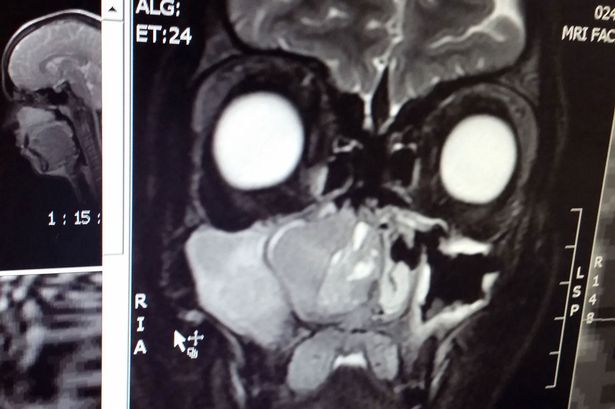

Jannine McHaffie, một bà mẹ trẻ 25 tuổi, đến từ Chelmsford, Essex, được chẩn đoán bị ung thư vòm họng ở dạng ung thư biểu mô (hay còn gọi là ACC). Các bác sĩ đã phải gỡ bỏ xương hàm, răng hàm trên, các phần xương má và hàm trên bên phải của cô.

Căn bệnh này ảnh hưởng đến các tuyến nước bọt, được phát hiện sau khi các bác sĩ tìm thấy một khối u có kích thước như quả dâu tây ở trong mũi của cô. Tuy nhiên, trận chiến chống ung thư khổ cực được bắt đầu từ khi cô bị chẩn đoán nhầm nghiêm trọng.

Bác sĩ phẫu thuật John Watkinson cho biết: “Ung thư biểu mô (ACC) là một bệnh ung thư tuyến nước bọt hiếm gặp, thường xảy ra ở vùng đầu và cổ. Bệnh nhân thường có dấu hiệu bị khối u và đau. Bệnh nhân được điều trị bằng phẫu thuật cắt bỏ và sau đó là dùng sóng vô tuyến điều trị”.